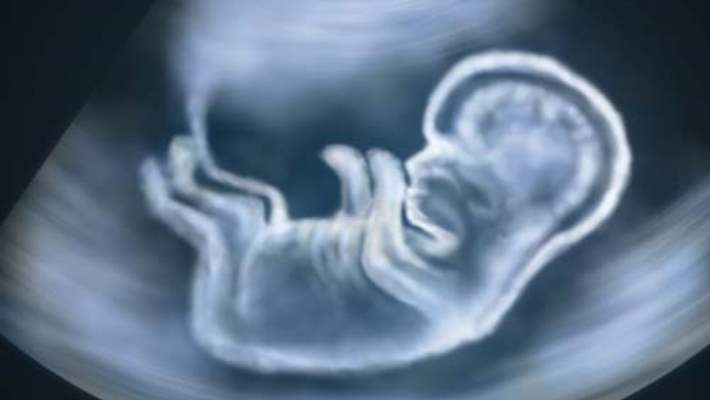

Hamileliğin hangi döneminde ve ne için olursa olsun, anne adayının kullanacağı her ilaç doktor kontrolünde olmak zorundadır. Bu bir antibiyotik için de bir ağız gargarası için de geçerlidir ve bunun bir istisnası yoktur. Hamileliğin ilk 3 ayı, hem anne adayı hem kadın doğum uzmanı ve hem de diğer branştaki doktorlar açısından, en önemli süreçtir. Çünkü bebeğin organ taslaklarının geliştiği dönemdir. Her türlü problemde doktor kontrolü zorunludur. Bunun yanı sıra anne adayının sağlığıyla ilgili sorunları ya da sistemik hastalıkları olabilir. Bu rahatsızlıklar hamileliği ya da bebeği riske sokacak olursa, mutlaka doktorlar tarafından müdahale edilmektedir. Burada öncelik sıralaması annenin hayatı ve çocuğun hayatı biçimindedir. Örneğin eğer kullanılacak ilaç bebeğin dişlerinde renklenmeye yol açıyorsa, anne ve bebek hayatı öncelikli olduğu için, bu renklenme göze alınabilmektedir. Hamileliğin ilk 3 ayı boyunca, dişeti ve diş sağlığı açısından da herhangi bir ilaç kullanılması önerilmemektedir. Ancak anne ya da bebek açısından hayati bir durum söz konusu ise, ilaç kullanımı gerçekleşmekte ve dişlerde oluşabilecek bir sorun göze alınmaktadır.

Hamilelik Sırasında Bebeğin Diş Sağlığı Hangi Koşullarda Riske Atılabilir?